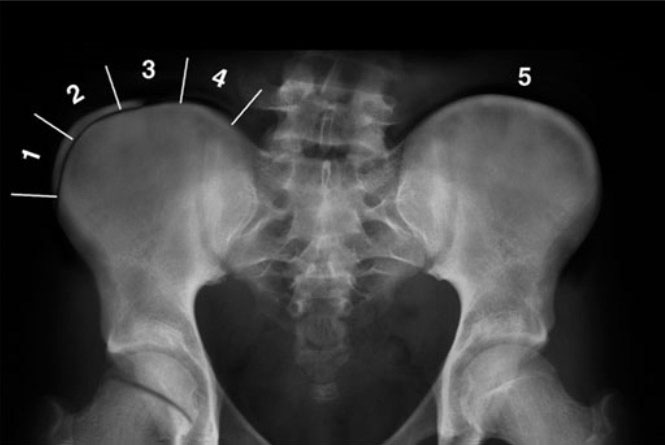

O índice de Risser é uma forma de avaliar a maturidade óssea pela ossificação da crista ilíaca no raio-X. Ele varia de 0 a 5:

- Risser 0: início do estirão de crescimento.

- Risser 1–2: fase de crescimento rápido.

- Risser 3–4: maturação óssea avançada, crescimento desacelerado.

- Risser 5 : Fim do crescimento ósseo.